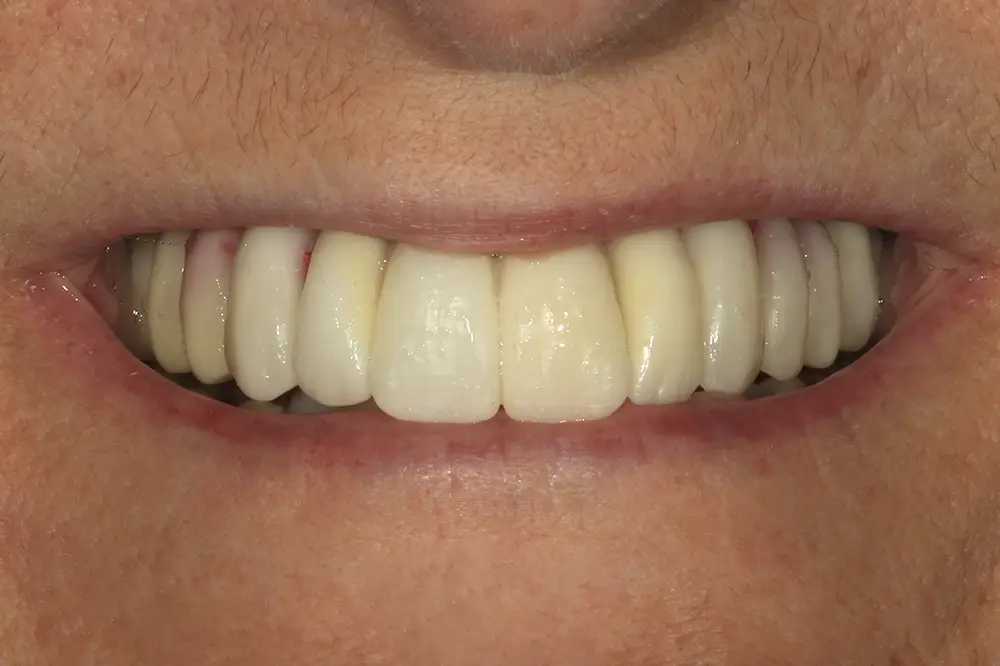

Para los sectores posteriores, se fabricaron estructuras mediante fresado CAD/CAM del mismo modo que la barra anteriormente descrita, con la diferencia de que sobre ellas se colocó un recubrimiento de cerámica (figs. 47-49). La paciente continúa en seguimiento, sin evidenciarse pérdidas óseas significativas en ninguno de los implantes estrechos y cortos que conforman la restauración de todo el maxilar superior tras tres años de carga de la prótesis definitiva (y hasta 4,5 de la carga de los implantes de la fase inicial de carga inmediata) (fig. 50).

Figs. 47 y 48. Prótesis terminadas, colocadas en la paciente.